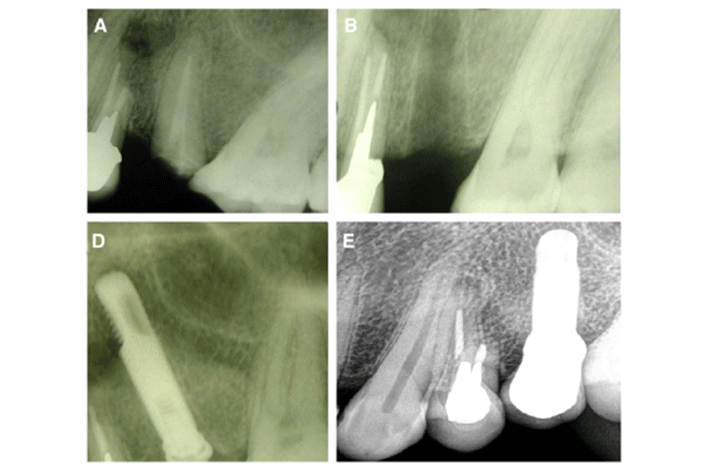

Now online in the Journal of Prosthodontics, Dr. Assery evaluated the treatment outcome of immediate implants placed in fresh extraction sockets without bone augmentation after 22 years of function. Twenty-nine out of thirty-five original subjects were included in this retrospective study. Implant treatment outcomes were evaluated using clinical and radiographic parameters obtained during follow‐up visits at 1, 5, 10, 15, 20, and 22 years after prosthetic loading.

One patient lost the implant during the osseointegration period, but no other implant failures or complications were reported. The cumulative survival rate during the 22‐year follow‐up was 97.2%.

This survival rate after a 22‐year follow‐up indicates an excellent prognosis for an immediate implant placed in fresh sockets without bone augmentation procedures. The successful clinical outcome of implant therapy is crucial from a life perspective for both subjects and the dental profession.